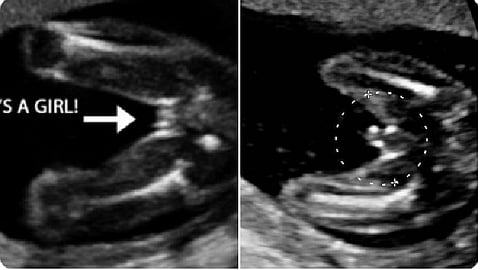

وأشارت في تغريدة عبر حسابها الرسمي على تويتر، إلى أن تحديد جنس الجنين يعتمد على رؤية الأعضاء التناسلية بالأشعة.

1 - نوعية جهاز الأشعة «متطور/قديم».

3 - وضعية الجنين.

4 - خبرة الطبيب.